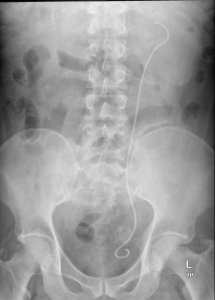

I rode 25km on the trainer on the 8th February 2011. So that night when I suffered acute abdominal pain, I thought it was intestinal obstruction due to old surgical adhesions. It happened once before in November 1993 after shifting house. The increase in exertion caused the scar tissues to strangulate the intestinal loops. Since it was at night, I persevered against the pain and waited for daylight before driving myself to the UKM Hospital. Hoping for the best, I did all the necessary investigation including abdominal X-ray (to look for air/fluid level) and Urine FEME.

The X-ray report came back as “no abnormalities detected”.

But the Urine FEME came back positive for RBCs, so my provisional diagnosis shifted towards urolithiasis. I downloaded the X-ray film and e-mailed it to a surgeon in Hospital Kuala Lumpur. He confirmed my suspicions by replying, “Congratulations, you got triplets!”.